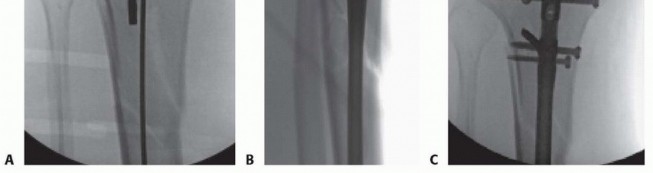

### TECH FIG 9 • A. A drill bit is used to ensure the guidewire is placed centrally in the distal segment of this distal metadiaphyseal fracture. B,C. The nail length guide is pushed to the opening of the tibia and verified with lateral fluoroscopic imaging. Device manufacturers supply nails in variable increments. When a length measurement falls in between lengths, choose the shorter length. A threaded end cap (usually 5, 10, and 15 mm) can be used if it is desired to bring the nail to top of the canal opening. Leaving the nail countersunk below the bone surface does not compromise stability in middle and distal fractures but may complicate future nail extraction. 558 Reaming the Canal Before reaming, estimate the narrowest canal diameter using both AP and lateral plain radiographs. Alternatively, intramedullary reamer sets typically have a radiolucent ruler that allows for intraoperative fluoroscopic verification, which should be done on both the AP and lateral views. The canal typically is reamed at least 1 mm over the isthmic diameter to minimize the risk of nail incarceration. Reaming should begin with an end-cutting reamer—the 8.5- or 9-mm size in most systems. Reamer heads should be evaluated before insertion and should be sharp and free of defects. Insert the reamer head into the proximal metaphysis with the knee in maximal flexion before applying power to avoid distorting the entrance hole ( TECH FIG 10A). Reamers are advanced at a slow pace under full power. If the reamer shafts are not solid, but are wound, be sure to avoid using reverse when drilling because that would cause the reamers to unwind if resistance is encountered within the intramedullary canal. Care must be taken not to inadvertently extract the guidewire when the reamers are removed. Multiple techniques are used. First, manual downward pressure can be applied to the wire with specialized instruments, medicine cups, or cleaning cannulas ( TECH FIG 10B). Once the reamer has cleared the opening, it can be clamped and held in position ( TECH FIG 10C). For the minimally reamed technique, a single end-cutting reamer (usually 9 mm) is passed down the canal to ensure the smallest diameter nail can pass through the narrowest segment of the intramedullary canal. In an effort to minimize thermal damage to the endosteal cortex, reaming should be discontinued within 0.5 to 1 mm of hearing the reamer head catching (“chatter”) on the endosteal cortex. Care also should be used when there are butterfly or oblique fracture fragments. Continued reaming after encountering chatter may result in iatrogenic comminution and loss of reduction.

### TECH FIG 10 • A. Maintenance of maximal knee flexion protects the entrance hole from being inadvertently enlarged by the reamer. B. If the guidewire is rotating during reaming, it must be held down as the reamer is pulled back to avoid inadvertent removal of the guidewire. C. A clamp can be used to grasp the guidewire when the reamer head clears the soft tissues. Unreamed Technique Standard preparation technique is used for the starting hole, and the fracture is reduced. Precise evaluation of the lateral isthmic diameter is repeated, and a small-diameter nail is selected, typically in the 7- to 9-mm range. A good guideline is to use a nail 1 to 1.5 mm smaller than the narrowest measure of the isthmus on the lateral radiograph. If lateral plane imaging is suggestive of canal diameter very close to nail size, a single pass with an end-cutting reamer usually is performed to decrease the possibility of nail incarceration. The nail is inserted and impacted in standard fashion. If significant resistance is encountered when the nail reaches the isthmus, the nail is removed to avoid incarceration or iatrogenic fracture propagation. A reamer 0.5 to 1.0 mm larger than the nail is passed down the canal, and nail passage is attempted again. Nail Insertion Once the nail insertion handle is attached, pass a drill through the proximal screw insertion attachment and screw insertion cannulas before inserting the nail to ensure accurate alignment of the attachment jig. Maintain nail rotation during insertion by aligning the center of the insertion handle with the tibial crest. Consider internal rotation of the nail if distal AP interlocking bolts are deemed necessary to minimize damage to distal neurovascular structures. Maintain knee hyperflexion during nail insertion to minimize the risk of posterior cortical abutment and iatrogenic fracture. Impact the nail to the final depth using lateral plane fluoroscopy. Interlocking Bolt Insertion In simple transverse fractures, place distal interlocks first to allow for backslapping for interfragmentary compression and gap minimization. Usually, distal interlock bolts are placed medial to lateral. Position the leg in slight extension and stable neutral rotation. 559 Rotate the C-arm to lateral imaging position and pull the tube back away from the medial side of the leg to allow for drill placement. Rotate the leg and C-arm individually and sequentially to create a perfect circle image; optimize this view before drilling attempts ( TECH FIG 11A). After localizing the interlocking hole using a clamp and fluoroscopy, make an incision large enough to place the locking bolt. Use blunt clamp dissection until the cortex is reached. Use a sharp drill point and place the center of the point in the center of the circle. Hold the drill obliquely to the nail axis to simplify repositioning ( TECH FIG 11B). Once the central location is achieved; align hand and drill with imaging axis. Fluoroscopes with laser alignment guides can be helpful to assist with alignment by centering the laser on the skin incision and then placing the laser in the center of the back of the drill when preparing to drill the hole ( TECH FIG 11C). Drill to the midsagittal point in the tibia. Then, disengage the drill from the drill bit and check the fluoroscopic image. If the drill is accurately positioned in the center of the hole, advance the drill bit with power through the far cortex; avoid broaching the far cortex by impacting with a mallet to avoid iatrogenic fracture. Drill the second interlock hole using the same technique but maintaining a parallel axis with the first successful drill passage. Replace the drill with the appropriate depth gauge and check an AP image before screw length selection. Once interlock lengths and position are verified, “backslapping” can occur to optimize compression. Using the slotted mallet attachment on the insertion handle, superiorly directed mallet blows can be used while pressure is applied to the foot in order to compress the fracture site. Fluoroscopy should be used to monitor the amount of compression and the nail position proximally. If backslapping is planned, the nail should be slightly overinserted to avoid nail prominence after compression is performed.